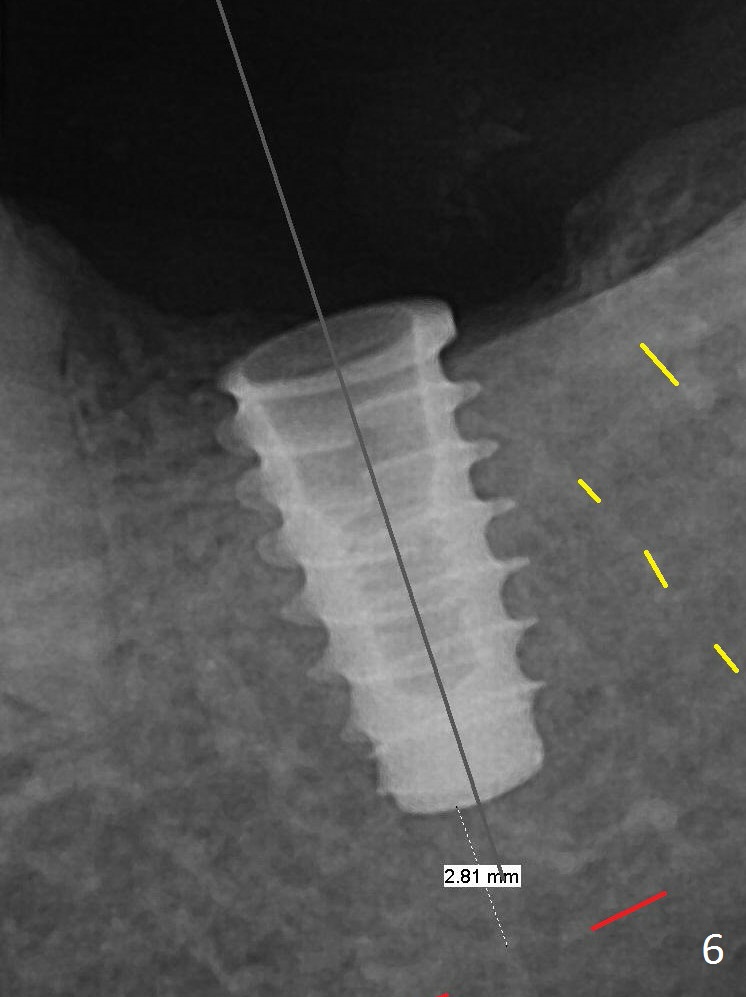

There is chewing pain in spite of previous occlusal adjustment 7 months post cementation (Fig.11-13: increased radiolucency around the implant). The crown/abutment is removed and a healing abutment is placed (6x3 mm); the implant is found to be stable. The patient will return for re-evaluation in 3 months. Check proximal contact after crown reseating. Occlusion should be light, since #18 is the only molar with a natural opposing tooth (heavy occlusion). The patient return for re-evaluation in 3 months (15 months postop); radiolucency appears to reduce (Fig.14). But there is pain when the healing abutment is being removed. After local anesthesia, the implant is removed with a wrench.